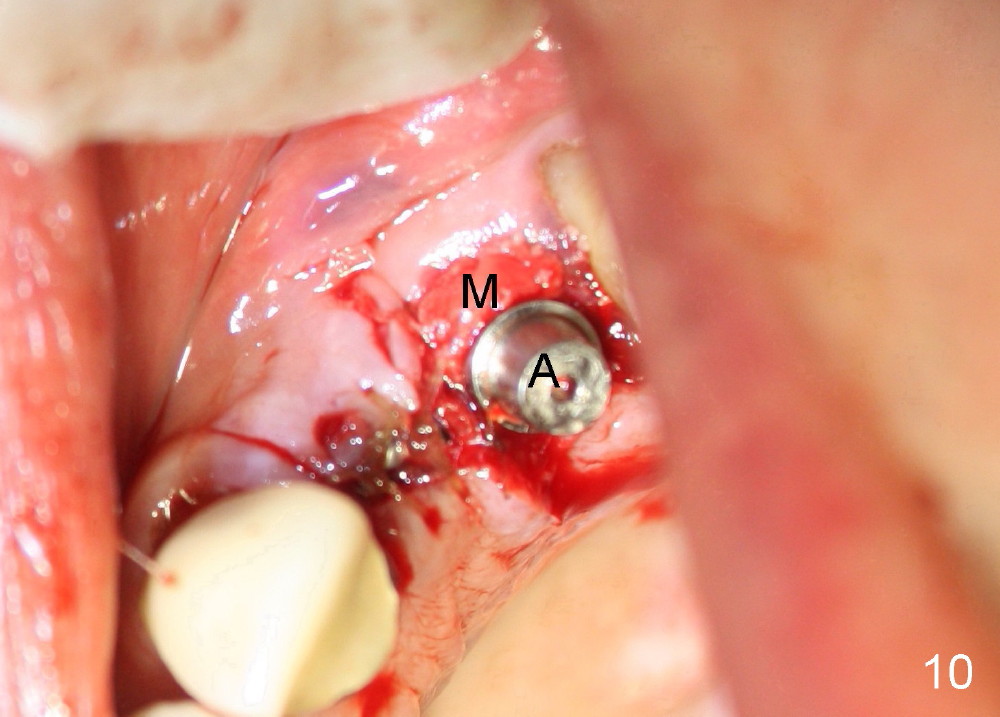

The anterior retainer is kept as a crown at #11 (Fig.2: C), whereas the residual root at the site of #13 is extracted with apical perforation (Fig.3 ^). It is confirmed by Fig.4 (<). To close the perforation, an osteotomy is initiated on the palatal wall of the socket with a 2 mm osteotome (Fig.5 insert: circle). As the osteotomy is being enlarged by a 3 mm osteotome, the bone between the original socket and the osteotomy is being pushed buccally. The former is being closed (Fig.5). The osteotomy is finished with combination of osteotomes and reamers. Fig.6 shows that a 5x14 mm tap is inserted at the site of #13 and that the sinus floor is lifted. In fact the sinus membrane is partially torn at the osteotomy, which is repaired by insertion of Colla-form Dressing (Impladent), followed by autogenous bone (harvested from reamers) mixed with Osteogen (Impladent). A 5x14 mm implant is placed at the site of #13 with insertion torque more than 60 Ncm (Fig.7: I). An incision is made at the site of #12 to start osteotomy with insertion of a parallel pin (Fig.7 P). A 3 mm reamer is kept in place for position confirmation (Fig.8 R). Due to ridge atrophy (Fig.2 arrowheads), a much smaller, but longer implant is placed at the site of #12 (Fig.9: 4x17 mm). The autogenous bone harvested from #12 osteotomy is placed in the buccal gap of #13, followed by insertion of Colla-form Dressing (Fig.10 M). To protect the membrane, a short abutment (4x3 mm) is temporarily placed (Fig.9,10 A) and perio dressing (Fig.9 D) is applied around the abutment and the interproximal areas of the neighboring teeth. Usually perio dressing dislodges around 1 week postop, particularly for a large edentulous space. In this case, the dressing is quite stable 11 days postop: the abutment (Fig.11 A) appears to contribute to retention of the dressing (D).